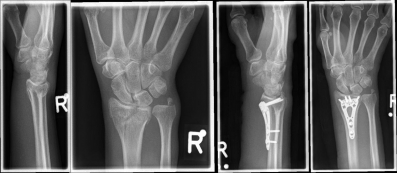

Handgelenk 1Often the inspection of the wrist already shows a suspected diagnosis. The accident mechanism must be clarified and after the physical examination, X-ray images of the wrist must be made in 2 levels.

In the classification of the distal radius fractures, the position of the fracture as well as a possible involvement of the articular surface are considered. Furthermore, the accident mechanism allows a classification of the fractures: the fall on the outstretched hand leads to a so-called extension fracture (Colles fracture), while the fall on the bent hand leads to a flexion fracture (Smith fracture).

Handgelenk 2The most common classification according to the Association for Osteosynthesis in fractures without involvement of the articular surface (A-fracture), fractures with partial joint involvement (B-fractures) and fractures with complete joint involvement (C-fracture). This results in indications for the therapeutic procedure.

Handgelenk 3

Pictures: A distal radius fracture with joint involvement (C-fracture) was treated with a plate osteosynthesis. After surgery, the plaster can be removed and physiotherapy exercises can be performed.

Complicated fractures involving the articular surface or dislocation should be surgically treated. Open fractures in which the skin is injured and bone is exposed require immediate surgical care. An involvement of the articular surface can lead to a restriction of the mobility in the wrist and therefore requires an anatomically exact reduction. The standard procedure for distal radius fractures is the provision of a titanium plate applied by the diffraction-side (palmar plate osteosynthesis) or the application of an external holder (external fixator).